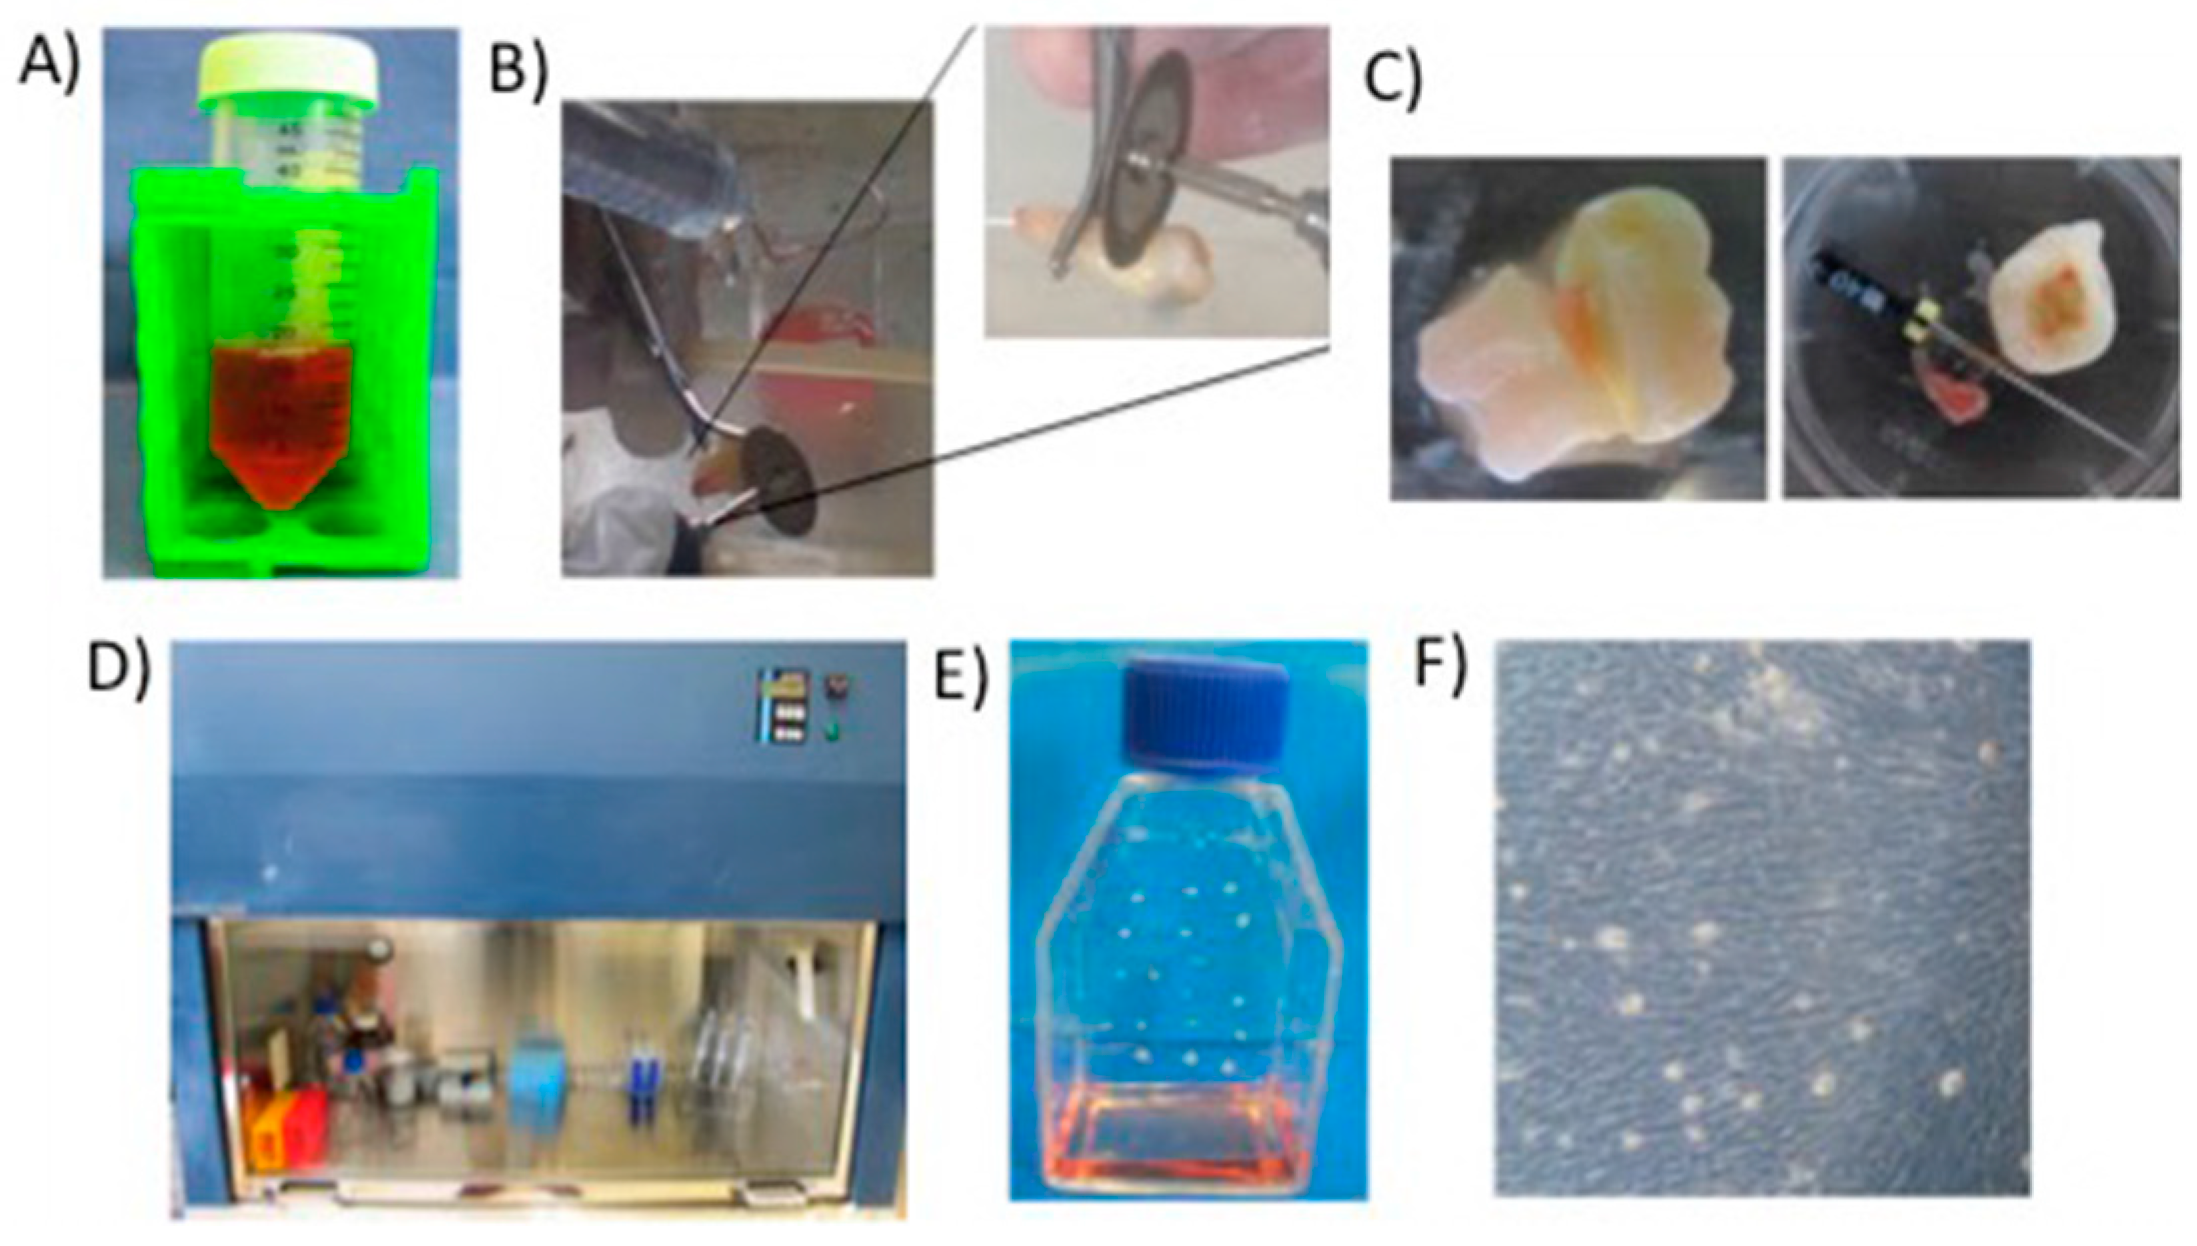

7.2. DPSC Viability on Scaffolds

7.3. Rat Calvarial Defect Model and Implantation of the Scaffold